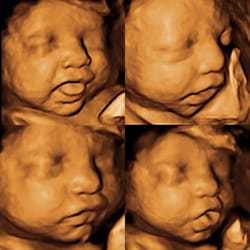

See Your Baby in 3D/4D/HD

With our Customizable 3D/4D/HD Ultrasound Experience for only $99